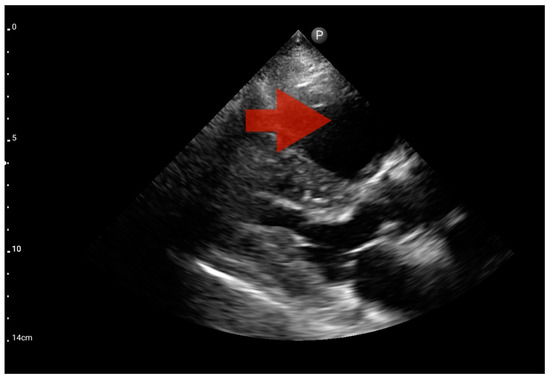

Figure 13.

Right ventricle enlargement; position: parasternal long axis (FATE protocol). Sector probe; the right ventricle is marked with the red arrow, and a significant enlargement of the right ventricle is visible, with a shift of the interventricular septum towards the left ventricle, and an ultrasound picture suggesting pulmonary embolism (source: author’s material—DK).